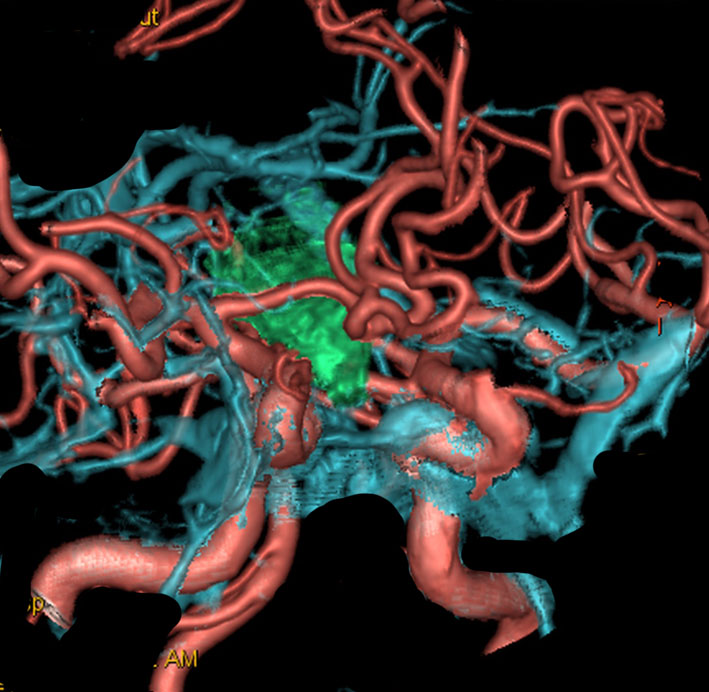

クラニオは鞍内や鞍上部という部位にできる腫瘍です。緑色に塗ったのが腫瘍,赤が動脈,青が静脈です。クラニオの周囲にはたくさんの動脈がありますが,特に内頸動脈と前大脳動脈が腫瘍に接していることが多いです。